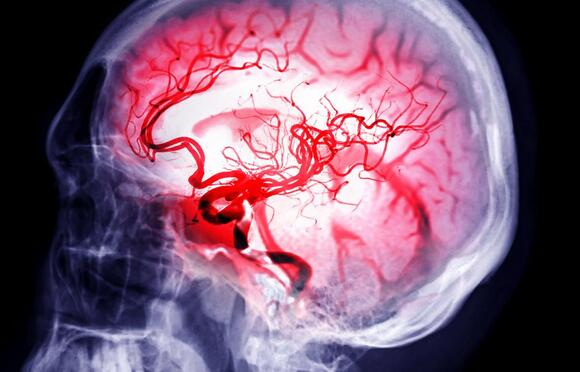

New study links surge in brain activity of dying patients to soul leaving the body

In a groundbreaking revelation, Dr. Stuart Hameroff, an anesthesiologist and professor at the University of Arizona, has proposed that a surge of energy observed in the brains of dying patients may signify the “soul leaving the body.” This assertion stems from a recent study that monitored a clinically dead patient’s brain activity using electroencephalogram (EEG) sensors, which recorded an unusual burst of energy after death.

During an interview with Project Unity on Tuesday, February 18, 2025, Dr. Hameroff explained that researchers detected this phenomenon in patients who had “no blood pressure” and “no heart rate.” He noted, “They saw everything go away and then [psh] you got this activity when there was no blood pressure, no heart rate.” This burst of activity, known as gamma synchrony—a brain wave pattern associated with conscious thought and awareness—was observed lasting anywhere from “30 to 90 seconds” after clinical death.

While some skeptics argue that this could merely be the “last gasp” of neurons firing or an illusion, Hameroff contends that it may represent consciousness departing from the body. He speculated that consciousness operates at a “deeper level” and does not require as much “energy consumption” as other brain functions, making it potentially “the last thing to go” during the dying process.

“The point is it shows that consciousness is actually, probably, a very low energy process,” he stated.

Dr. Hameroff credited Dr. Lakhmir Chawla for pioneering this monitoring technique in previous studies. Anesthesiologists have routinely employed EEGs to ensure there is no brain activity in organ donors before the harvesting process.

According to Hameroff, “This has been a fairly reproducible event; not 100% like 50% of patients show this when you measure it.”

Hameroff introduced the concept of “quantum level brain activity,” suggesting that certain brain functions may operate on a quantum scale beyond traditional neural pathways. This theory posits that consciousness could be a collective quantum vibration within neurons.